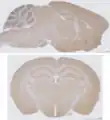

Sagittal section (top) vs. coronal section (bottom) of a mouse brain